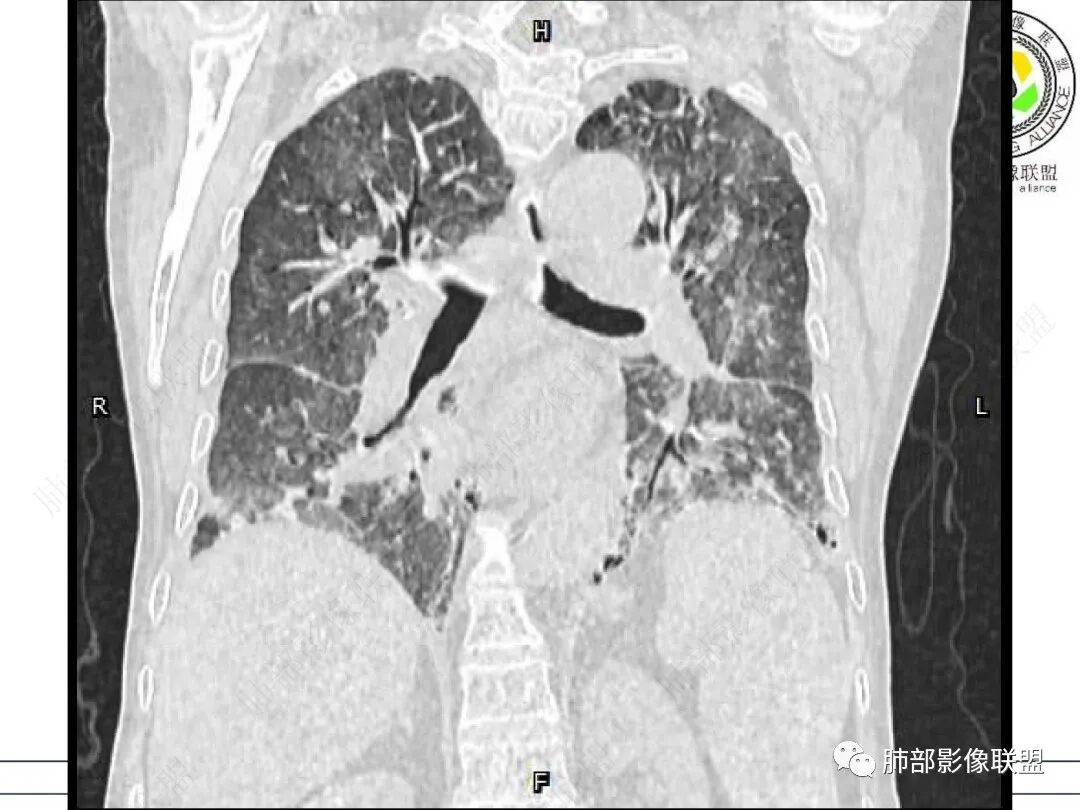

两肺叶后肋膈角区见多发蜂窝状结构破坏表现,双肺叶小叶间隔增厚,左肺上叶后段及舌段和右肺中叶胸膜炎性肉芽肿特点,双侧胸腔少量积液,有类风湿性关节炎治疗史,结缔组织相关性间质性肺病。

老年,外阴溃疡加发热,感染指标明显有异常,血气分析,过度呼吸及低氧血症,宿主因素,糖尿病和激素,基础疾病RA。影像,双下肺体积有缩小,有蜂窝?双肺磨玻璃,多发结节,双侧胸水。树芽不明确。是否有旧片,这个患者有UIP背景,是否感染或者UIP急性加重,或者基础上合并肺栓塞及肺水肿?长期激素,没有提供CD4细胞亚群,存在2种情况,1,风湿病没有压制住,肺考虑CTD相关性间质改变,压制过猛,结合感染指标,奴卡是有可能的。激素加糖尿病,结核也带排,激素加磨玻璃加G实验阳性,PCP也带排,临床信息太少,进一步排查

老年女性,有高血压糖尿病及类风湿性关节炎病史,发病前发烧。影像学两肺弥漫性磨玻璃影及斑片影,有渗出性病变亦有间质性改变,支气管血管束增粗,有牵拉扭曲有小气管扩张及间质增厚,两肺下叶胸膜下少许蜂蜜状影。两侧胸腔积液。考虑类风湿性关节炎肺内浸润?合并真菌感染?

老年女性,类风湿关节炎病史多年。发热。以两肺下叶为主弥漫磨玻璃及网格状透亮影,透亮度减低,局部小蜂窝状改变;两肺胸膜下散在几枚实性病灶;双侧胸腔积液。考虑RA-ILDNSIP

女,71,外阴疼痛2周,发热1周。类风关、高血压、高血糖、卵巢囊肿、肠粘连、胆囊结石等病史及相关药物治疗史。胸部CT:两肺弥漫磨玻璃,血管束增粗,两下肺后肋膈角多发蜂窝,对称分布,双侧胸腔少量积液,纵隔窗心脏大血管影明显增宽。考虑混合性病变,CTD-ILD,并肺水肿?并PJP?。

类风湿病史二十年,两肺弥漫性间质改变并肺内多发结节及双侧胸水,首先考虑结缔组织相关性疾病,CTD一lLD,双肺多发结节,外阴部多发溃疡,白塞氏病也要考虑

双肺下叶多发蜂窝影,双肺小叶间隔增厚,双肺磨玻璃影,双侧胸腔积液,有类风湿性关节炎,考虑结缔组织相关性间质性肺病,合并感染

GGO重力趋势明显,PJP重力趋势没这么明显

双侧中轴间质增厚。可惜大支气管层面不多。

1、部分小叶间隔增厚区没有GGO,最起码不支持局部GGO病变修复导致的间质增厚

GGO重力趋势明显,双侧胸腔积液,还是比较支持肺水肿类病变。

类风湿肺损害有,出血不太符合。PJP重力趋势没这么明显。而且上肺间质增厚区域没看到GGO。

①影像表现复杂:较弥漫间质性改变,对称磨玻璃密度为主,小叶间隔增厚,有一定重力分布趋势,未见明显纤维化,气囊及蜂窝位于肺边缘,未见典型“月弓征”。心脏影增大,双侧胸腔积液。

这即可见于间质性肺病,也可见于真菌感染(如PJP)、病毒感染,类风湿,以及肺水肿等等。

一般而言,如存在磨玻璃密度影浑浊,有重力分布趋势,肺表面蜂窝影,胸腔积液等等,并不常见于单纯PJP,除非其他因素叠加。

患者存在肺水肿应当是合理的解释。其他旁证还有,心脏影增大,肾小球滤过率降低,双侧胸腔积液等等……